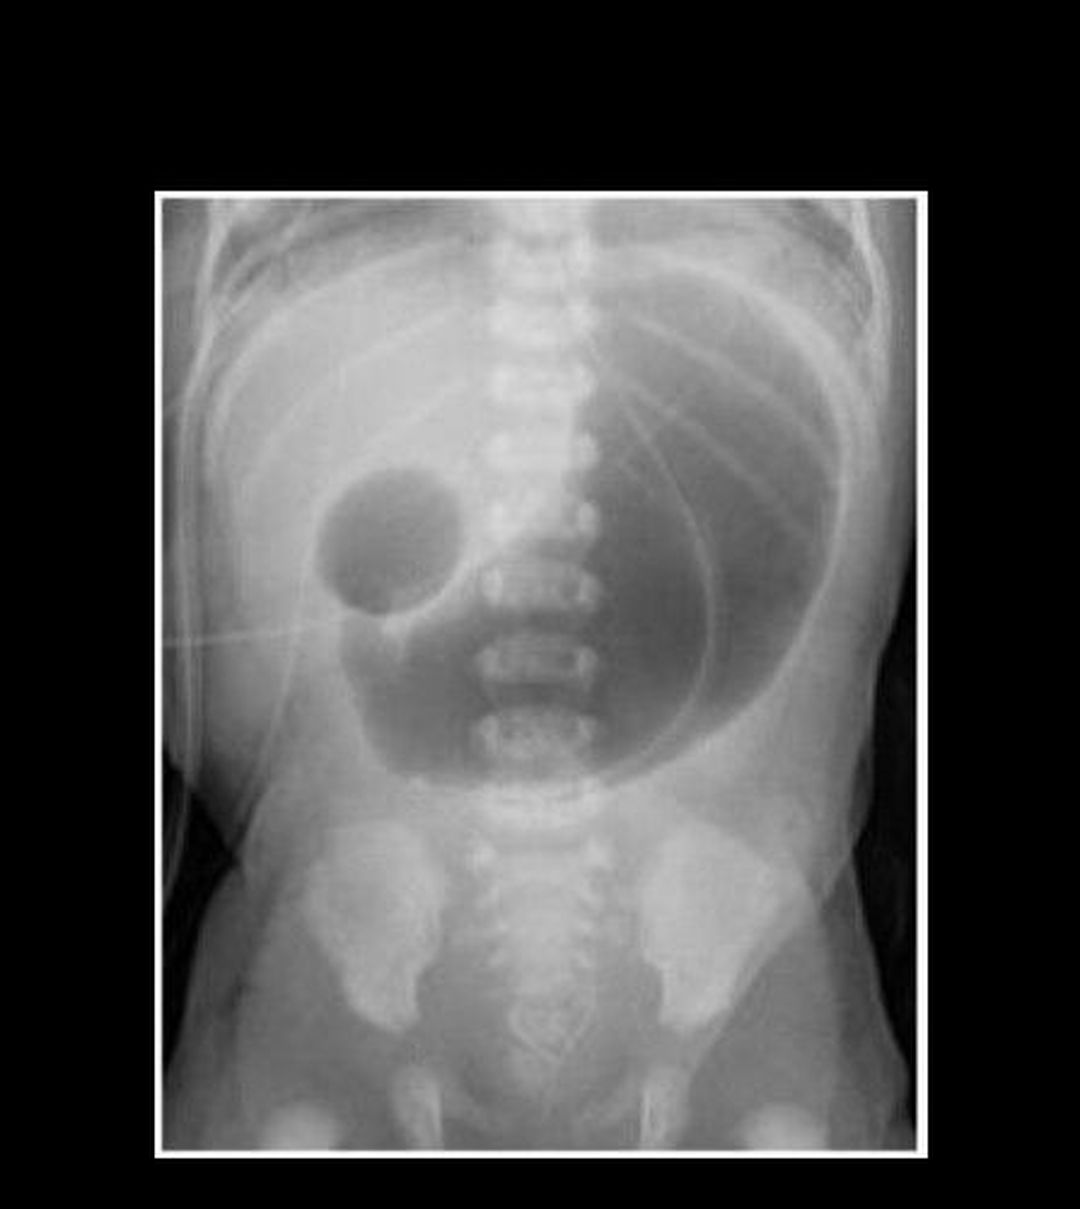

Radiography shows a distended stomach and distended duodenum, which are separated by the pyloric valve, a finding described as the double-bubble sign. This is characteristic of Duodenal atresia, also known as duodenojejunal atresia. The air is trapped in the stomach and proximal duodenum, which are separated by the pyloric sphincter, creating the appearance of two bubbles visible on x-ray. Duodenal atresiais the congenital absence or complete closure of a portion of the lumen of the duodenum. It causes increased levels of amniotic fluid during pregnancy (polyhydramnios) and intestinal obstruction in newborn babies.